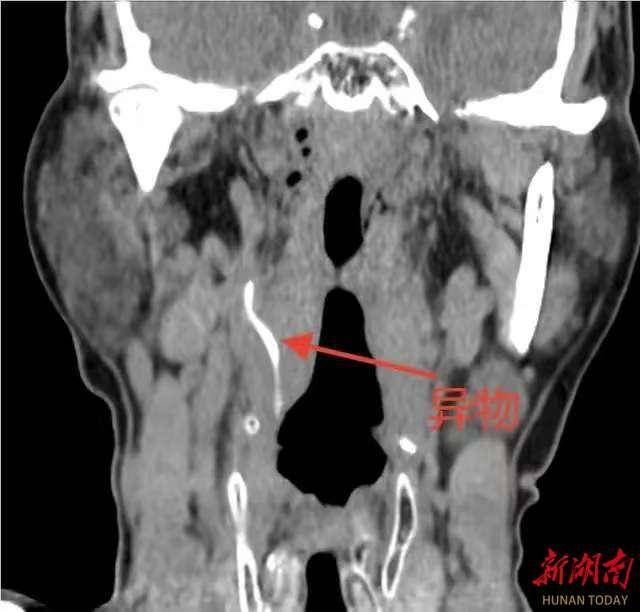

科主任陈志军接诊患者后,结合喉镜情况及详细询问病史,判断该异物可能已深入颈内间隙,经颈部CT三维重建检查,提示咽侧壁异物已穿破黏膜层,深入颈部间隙,且异物尖端距离右侧颈动脉分支仅毫厘之遥。颈动脉是大脑供血的主要通道,一旦被异物刺破或继发感染侵蚀血管,极易引发致命性大出血或脑卒中,手术风险极高。影像警示:异物如同一枚“定时炸弹”,静静地潜伏在颈动脉分支旁,每一次吞咽、颈部活动都可能带来不可预料的危险。面对如此棘手的情况,陈志军科主任迅速启动应急预案,组织血管外科、麻醉科进行多学科会诊。发现风险,经分析,异物位置较深,周围重要血管、神经密布,传统颈外径路手术创伤大、易损伤血管,且可能因术中移位导致二次伤害。

经反复评估,团队最终确定了经口全麻支撑喉镜下异物探查取出术的方案。该微创路径可直达咽部病灶,避免颈部切开,但要求术者具备高超的内镜操作技巧与稳定的心理素质,确保异物取出过程中零移位、零损伤。手术当日,在麻醉团队的保驾护航下,患者进入全身麻醉状态。陈志军科主任借助支撑喉镜充分暴露咽部,于高清内镜视野下,清晰见异物嵌顿处黏膜红肿,周围组织粘连紧密,并小心分离包裹异物的肉芽组织,轻柔松动异物嵌顿方向。